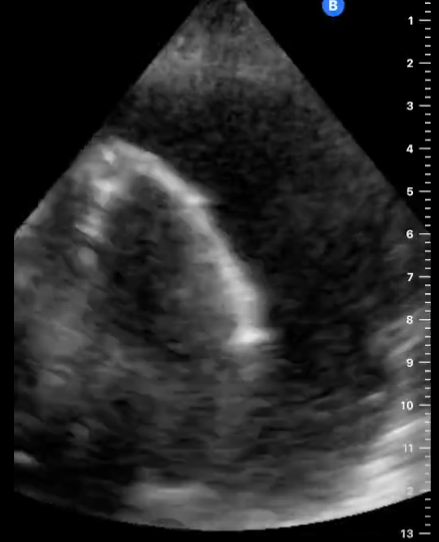

En la ecocardiografía se aprecia latido cardiaco con intercambio de flujos muy disminuido y el miocardio movilizándose en el interior del derrame pericárdico contenido sin taponamiento.

En este caso tenemos un cuadro de derrame pericárdico con repercusión hemodinámica pero apreciándose latido cardíaco y suficiente contractilidad como para no incurrir en taponamiento cardíaco que hubiera supuesto una emergencia vital para la paciente.